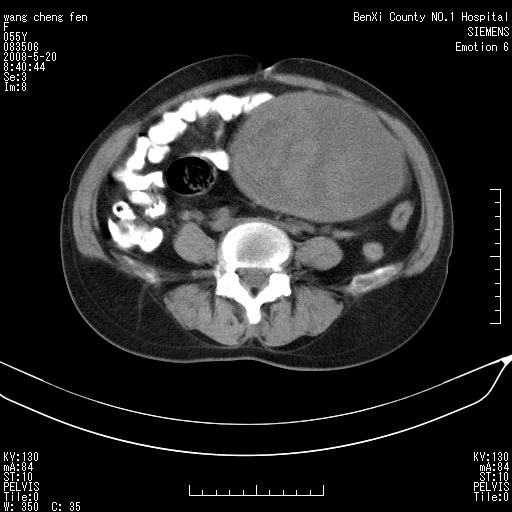

女、绝经后阴道流血3个月

左侧附件区可见一囊性占位,边缘清楚,内可见不规则形软组织影 ce:囊壁及内部可见强化 考虑 卵巢囊腺瘤

左侧附件区巨大囊实性病灶,边缘光整,病灶囊壁较厚,增强示囊壁及实性部分明显强化,强化呈度与宫体实质大致相同,宫腔积液征像,未见盆腔积液等其他异常,考虑左侧卵巢囊腺癌,不除外囊腺瘤及浆膜下肌瘤坏死

左侧附件区巨大囊实性病灶,边缘光整,病灶囊壁较厚,增强示囊壁及实性部分明显强化,强化呈度与宫体实质大致相同,宫腔积液征像,未见盆腔积液等其他异常。绝经后阴道流血3个月,结合病史左侧卵巢囊腺癌首先考虑,宫腔扩大不除外累及。期待结果。

支持浆膜下子宫肌瘤.之前由于网络原因未看全图片,现在重看,宫颈见一类圆形低密度影,增强轻度强化,低于肌层强化,宫腔扩大,考虑宫颈癌伴宫腔积液可能性大.

囊实性肿块分隔厚度较大,厚薄不均,增强实性成分明显强化,有不规则阴道流血,卵巢囊腺癌可能性大。

1,宫颈部占位,宫颈癌?2,左侧附件区囊实性占位,界较清,实质部分强化明显。考虑浆膜下或阔韧带肌瘤囊变可能大。囊腺类肿瘤不除外。